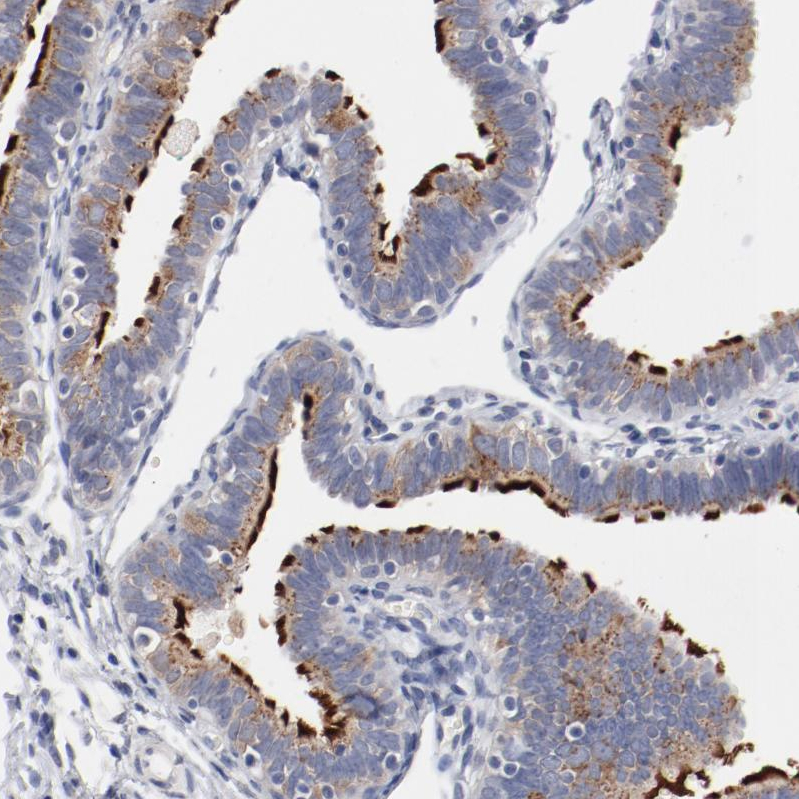

Immunohistochemistry analysis in human fallopian tube and lymph node tissues using HPA003543 antibody. Corresponding AK7 RNA-seq data are presented for the same tissues.